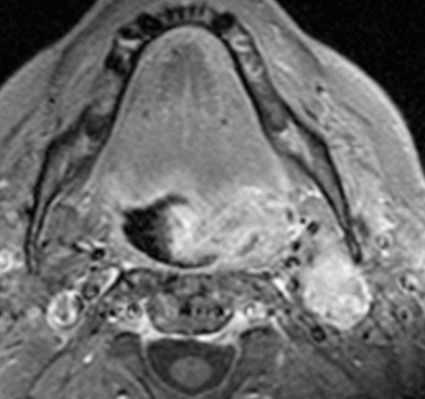

(Слева) КТ с КУ, аксиальная проекция. Злокачественная фиброзная гистиоцитома жевательного пространства и нижней челюсти. Солидная опухоль, которая умеренно накапливает контраст, располагается в правом жевательном пространстве и разрушает нижнюю челюсть, в том числе ее ветвь и тело. Жевательное пространство представляет собой глубокую область лица, в которой может возникать саркома.

(Справа) КТ с КУ, аксиальная проекция, тот же пациент. Солидная опухоль, умеренно накапливающая контраст, разрушает значительную часть нижней челюсти.

(Слева) МРТ Т1ВИ FS с КУ, аксиальная проекция. Лейомиосаркома жевательного пространства высокой степени злокачественности. Опухоль неоднородно накапливает контраст и прорастает в нижнюю челюсть. Только по данным лучевой диагностики дифференцировать различные типы сарком невозможно, за исключением случаев обнаружения матрикса остео- или хондросаркомы.

(Справа) МРТ Т1ВИ FS с КУ, коронарная проекция, тот же пациент. Новообразование, накапливающее контраст, распространяется в полость черепа через овальное отверстие. Отсюда опухоль может прорастать в пещеристый синус.

(Слева) На аксиальной КТ с КУ в жевательном пространстве справа визуализируется злокачественная фиброзная гистиоцитома нижней челюсти в виде минимально контрастирующегося солидного объемного образования, разрушающего ветвь и тело нижней челюсти. Жевательное пространство является известным местом возникновения сарком глубоких областей ли ца.

(Справа) На аксиальной КТ с КУ у этого же пациента визуализируется опухоль в жевательном пространстве справа, приводящая к обширной деструкции нижней челюсти. Обратите внимание на асимметрию лица на стороне поражения.

(Слева) На аксиальной МРТ (Т1 ВИ C+) в жевательном пространстве визуализируется лейомиосаркома высокой степени злокачественности, неравномерно накапливающая контраст и поражающая нижнюю челюсть. Большинство типов сарком жевательного пространства сложно дифференцировать в отсутствие костного или хондроидного матрикса.

(Справа) На корональной МРТ (Т1 ВИ С+ FS) у этого же пациента визуализируется контрастирующаяся опухоль с интракраниальным распространением через овальное отверстие а и поражением кавернозного синуса.